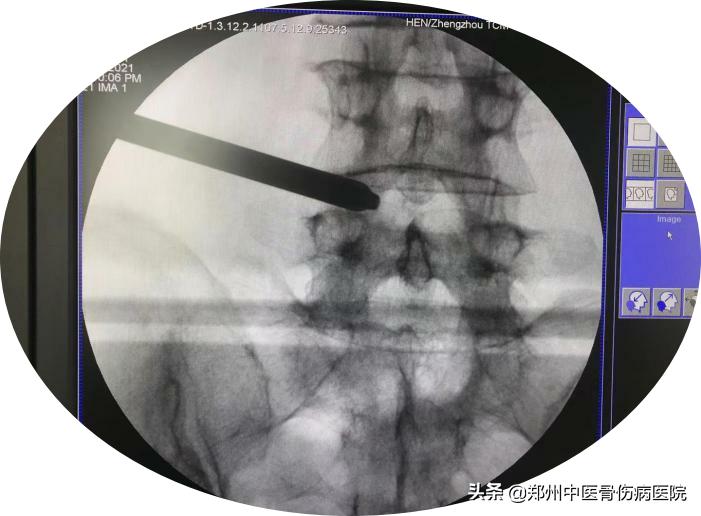

半个月前双腿也开始疼痛,尤其是左臀部疼痛麻木,不能久站久坐,贴膏药也没有改善,听亲戚介绍她来到了郑州中医骨伤病医院,经过检查发现,秦阿姨腰4-5节段腰椎间盘突出伴侧隐窝狭窄。

在结合病情与检查结果,给出了秦阿姨的治疗方案——进行经皮内镜椎间盘切除手术即俗称的 椎间孔镜手术。

近年来随着经皮椎间孔镜(PELD)技术在国内迅猛开展,这是一项开展成熟的微创脊柱外科内镜技术,也是一项充满崭新生命力的新技术。该技术是真正意义上的脊柱内窥镜系统,内窥镜直视下操作可清晰、完整摘除突出组织或脱垂髓核清除骨质增生、治疗椎管狭窄症、同时该套设备配备了360度射频刀头能够在术野内利用射频技术修补破损的纤维环;脊柱周围肌肉、韧带、骨性结构得到最大程度保护脊柱稳定性;创伤小、恢复快、安全性高。

培养椎间孔镜在安全工作三角区实施手术,在椎间盘纤维环之外做手术在内窥镜直视下可以清楚的看到突出的髓核、神经根、硬膜囊和增生的骨组织。然后使用各类抓钳摘除突出组织、镜下去除骨质、射频电极修复破损纤维环。手术创伤小:皮肤切口仅7mm,如同一个花生大小,出血不到20m,术后仅缝1针。

椎间孔镜通过在椎间孔安全三角区、椎间盘纤维环之外彻底清除突出或脱垂的髓核和增生的骨质来解除对神经根的压力,消除由于对神经压迫造成的疼痛。其手术方法是通过特殊设计的椎间孔镜和相应的配套脊柱微创手术器械、成像和图像处理系统等共同组成的一个脊柱微创手术系统。在彻底切除突出核的同时清除骨质增生、治疗椎管狭窄症、可以使用射频技术修补破损的纤维环等。